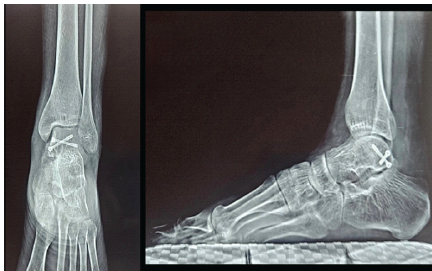

Reduction and fixation were confirmed clinically and fluoroscopically, followed by thorough irrigation and layered wound closure was performed and a sterile dressing was applied. Postoperatively, the limb was immobilized in a below-knee slab for 2 weeks, followed by a below-knee cast for an additional 4 weeks. The cast was removed at 6 weeks. Subsequently, ankle and subtalar range-of-motion exercises were initiated, along with toe-touch weight bearing, gradually progressing to full weight bearing by 8 weeks. At 1 year, follow-up radiographs confirmed satisfactory implant position with good progression toward complete bony union (Fig. 5). Clinically, the patient was asymptomatic and demonstrated full, pain-free ankle range of motion at 1 year review (Fig. 6).

Figure 5: Anteroposterior and lateral ankle radiographs at 1-year follow-up showing complete radiological union with maintained alignment.